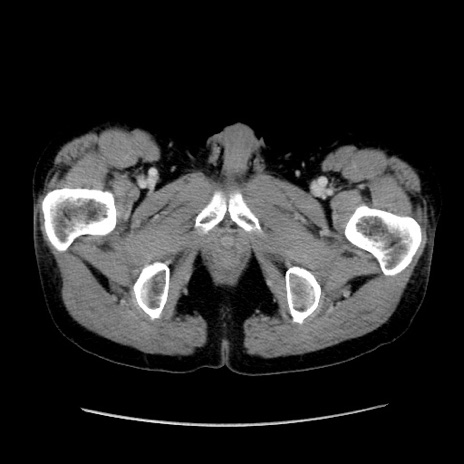

症例37(横断像)

【症例】40歳代 男性

【主訴】腹痛

【現病歴】4時間ほど前に電車に乗車中に臍部上より腹痛出現。徐々に増悪し起立困難となり、救急外来受診。生ものは数日食べていない。今朝お雑煮を食べた。

【身体所見】BT 36.8℃、BP 117/84mmHg、HR 91/min、SpO2 97%、苦悶様、腹部:臍上部広範囲圧痛あり、反跳痛±

【データ】WBC 8100、CRP 0.03